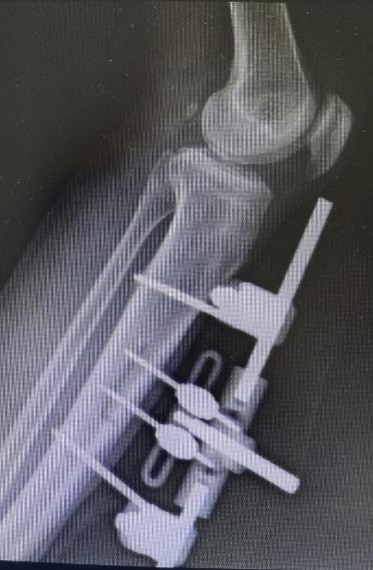

王瑞良主任团队经过详细检查发现,患者足底软组织大面积坏死,深部肌腱、骨质外露,合并严重感染。"当时患者已做好截肢心理准备,但考虑到他正值壮年且还有劳动需要,我们为其挑战保肢治疗。"王主任介绍,目前其手足显微外科开展"胫骨横向骨搬运术"已非常成熟,已成功为数十位患者“保肢”,该项技术通过精确调控骨骼微动刺激血管神经再生,且创伤小、恢复快,可以有效解决糖尿病足、下肢动脉硬化闭塞症的治疗难题。术后张先生肢体血运恢复良好,妻子红着眼眶回忆:"真的没想到可以保住他的脚,看着他的脚一天天变好,就像看到一家人希望。"

△胫骨搬运术前术后CTA血管对比,血管再生良好